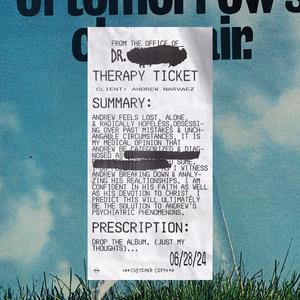

THERAPIST

Andrew Narvaez

THERAPIST

Andrew Narvaez